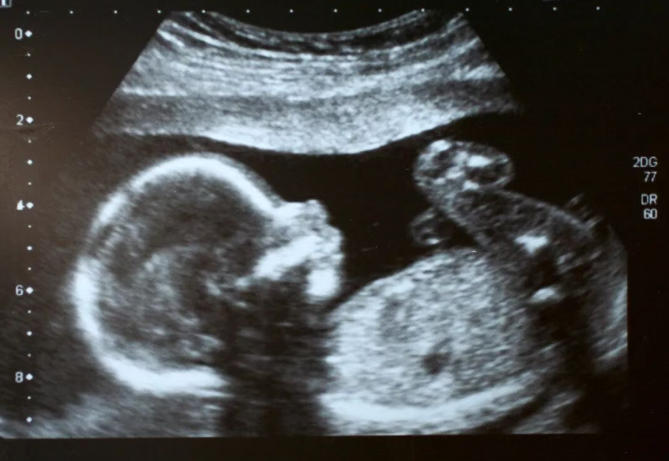

“鼻骨未显示”是指在当前超声检查中,没有清晰看到胎儿的鼻骨结构。但这绝不等于“宝宝没有鼻子”!

鼻骨是鼻梁的支撑骨骼,在超声图像上表现为一条明亮的短线。有时因为以下原因,可能导致暂时“未显示”: